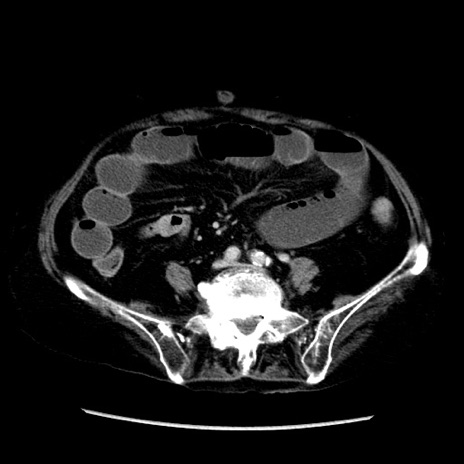

冠状断像

症例14(横断像)

【症例】 90歳代女性

【主訴】 腹痛・嘔吐

【現病歴】今朝から左側腹部痛を認めた。 経過観察していたが、嘔吐を認めたため来院。

【既往歴】 子宮癌術後

【身体所見】 意識清明、BP 127/54mmHg、P 98bpm Sp02 95%(RA)、BT 35.8°C、腹部平坦・軟腸ぜん動音聴取良好、右下腹部圧痛(+) 反跳痛なし

【データ】WBC 9800、CRP 0.46